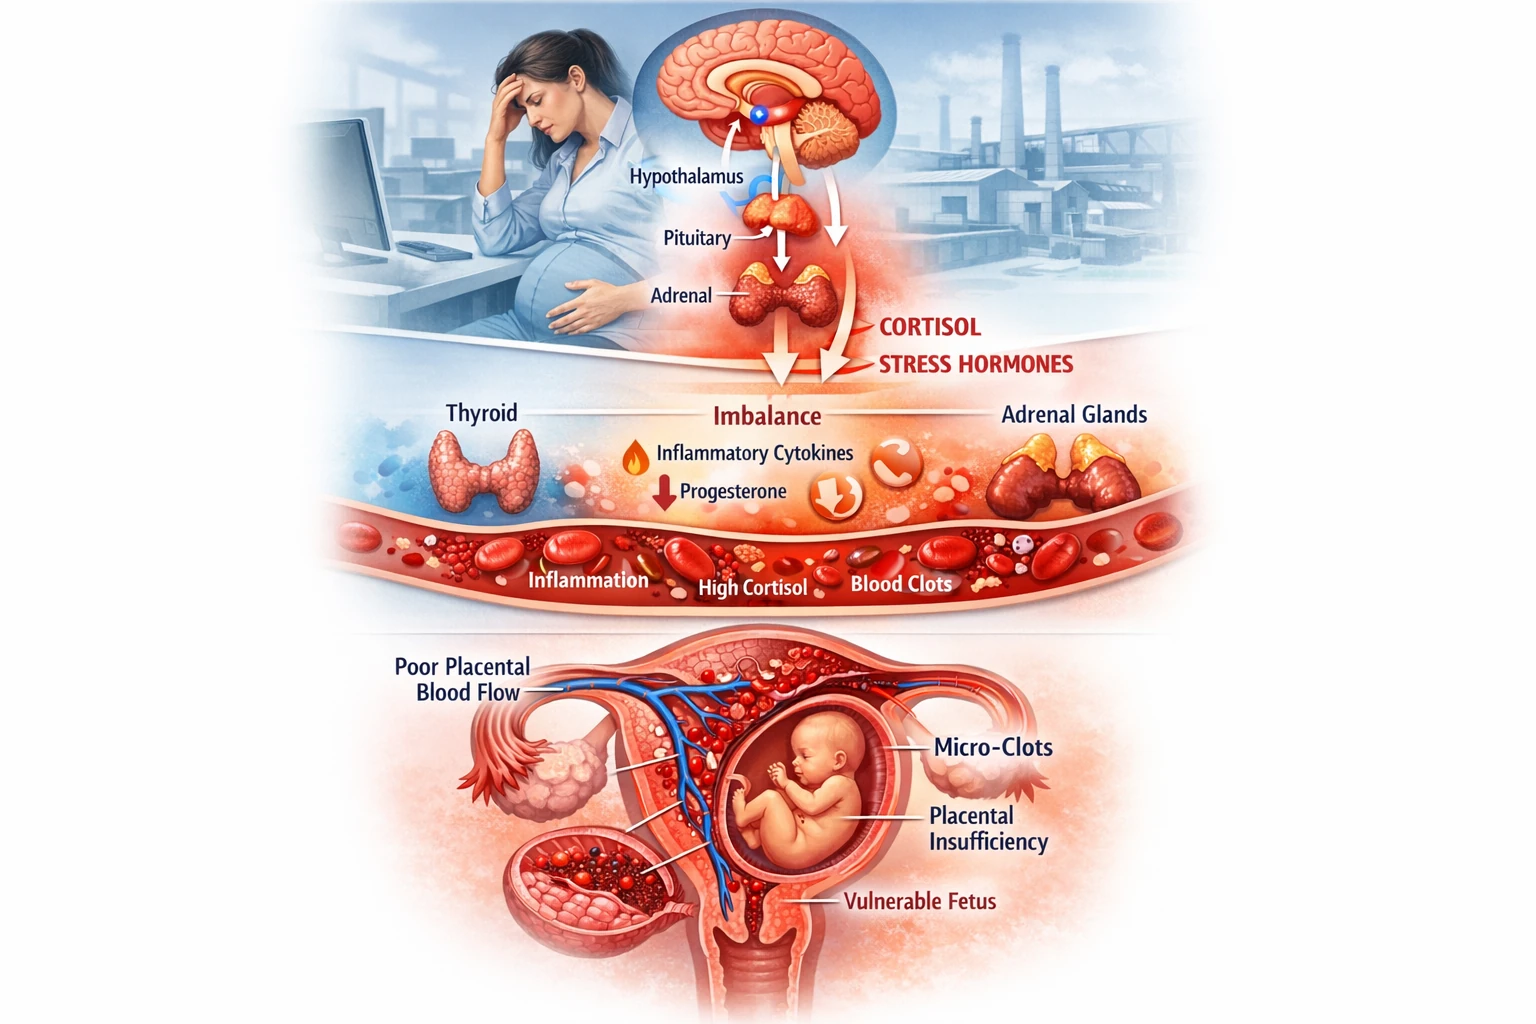

– تقویت التهاب میکروگلیال: کمبود ویتامین D منجر به فعالسازی میکروگلیا و آزادسازی سیتوکاینهای التهابی (IL‑۶، TNF‑α) میشود که اثر سموم را چندبرابر میکند.

– سرب (Lead): سبب کاهش کلسیتریول در مغز و مهار گیرنده VDR میشود؛ این اثر در افراد دچار کمبود ویتامین D دوچندان است.

– جیوه (Mercury): در غیاب ویتامین D، سمّیت اکسیداتیو آن افزایش یافته و مرگ نورونی در قشر حرکتی بیشتر میشود.

– آلومینیوم و منگنز: کمبود ویتامین D پاسخ التهابی مزمن را تشدید کرده و سبب افزایش فیبروز آستروسیتی در بافت مغز میشود.